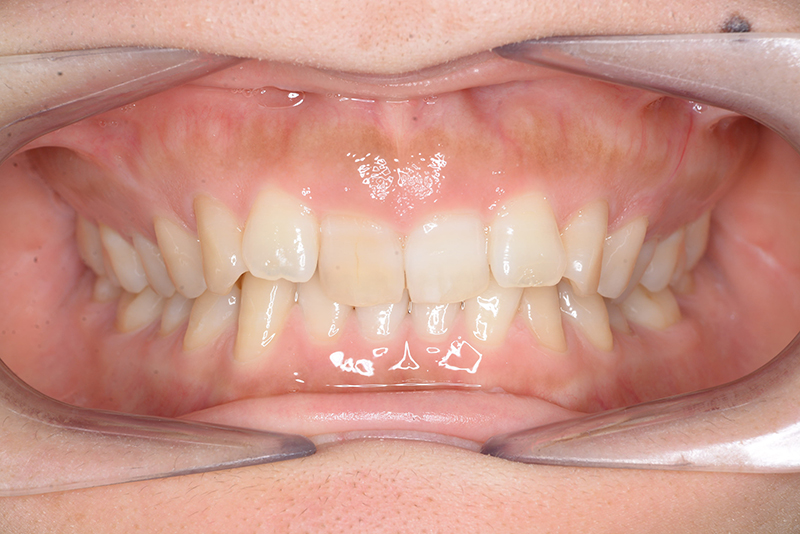

初診時

FP・IOP

主訴 噛み合わせが深い 診断名 アングルⅡ級2類症例

口腔内所見 大臼歯、犬歯関係はⅡ級で、上顎中切歯は舌側傾斜しており、over jet1.5mm,over bite 6.0mmいわゆるⅡ級2類であった。